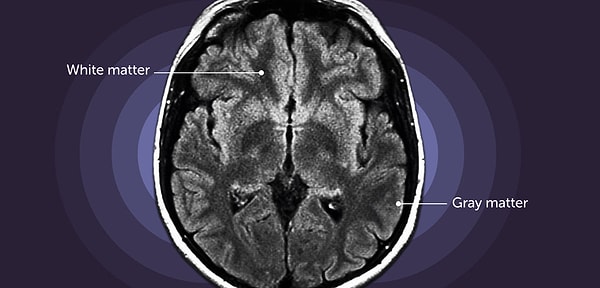

Yapılan yeni bir çalışma, hamileliğin beyindeki gri madde miktarında geçici bir azalmaya yol açabileceğini ortaya koydu.

Nature Dergisi'nde yayımlanan bir araştırmaya göre, İspanya'daki sinirbilimciler, gebelik hormonları ile beyindeki gri madde dalgalanmaları arasında bir bağlantı buldu. Bu bağlantının, doğum sonrası dönemi ve anne ile yenidoğan arasındaki bağları daha iyi anlamamıza yardımcı olabileceği belirtildi. Hamileliğin, beyindeki gri madde miktarında geçici bir azalmaya yol açabileceği kanıtlandı.

Çalışmaya katılan hamile kadınlar ortalama olarak beyinlerindeki gri maddenin yüzde 5'ini kaybetti. Bu durum, sosyal bilişi belirleyen bölgeler de dahil olmak üzere beynin geniş alanlarını etkiledi. Duyusal bilgilerin işlenmesine ve karar vermeye yardımcı olan beyin ve omurilik dokusu olan gri maddenin, hamilelik sırasında beyne akan sıvının artmasıyla sıkışabileceği kaydedildi.